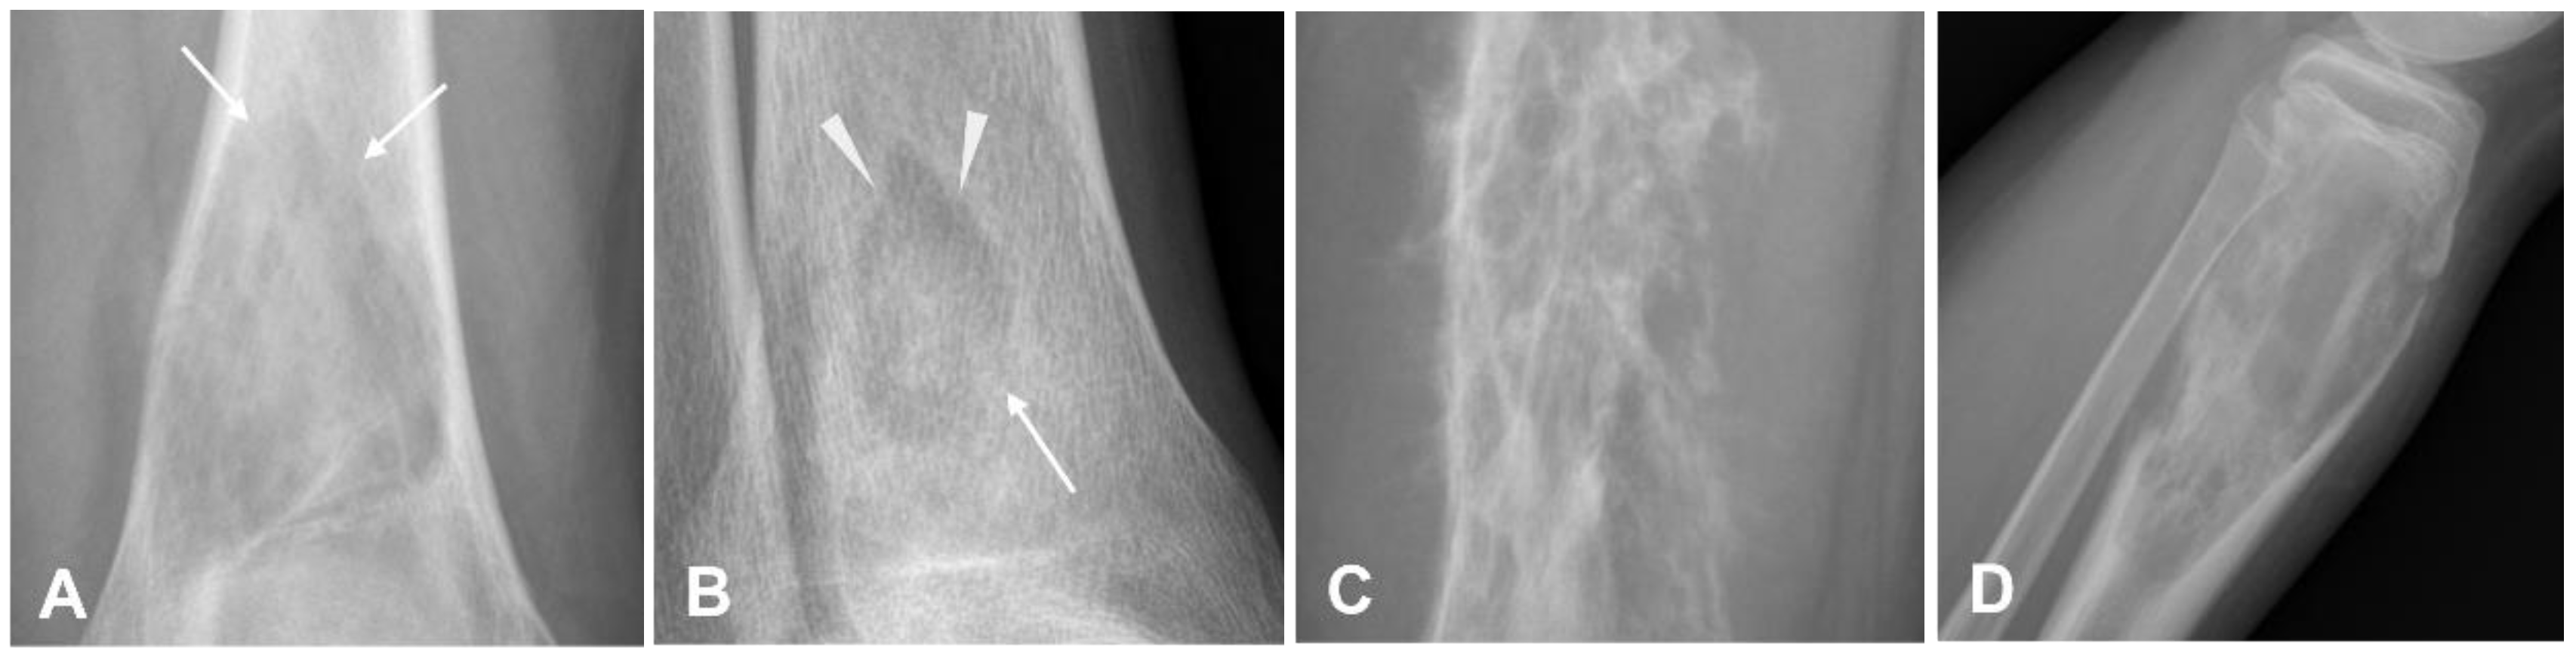

3.1.3. Teleangectatic Osteosarcoma

- Sangle, N.A.; Layfield, L.J. Telangiectatic Osteosarcoma. Arch. Pathol. Lab. Med. 2012, 136, 572–576. [Google Scholar] [CrossRef] [PubMed]

- Angelini, A.; Mavrogenis, A.F.; Trovarelli, G.; Ferrari, S.; Picci, P.; Ruggieri, P. Telangiectatic Osteosarcoma: A Review of 87 Cases. J. Cancer Res. Clin. Oncol. 2016, 142, 2197–2207. [Google Scholar] [CrossRef] [PubMed]